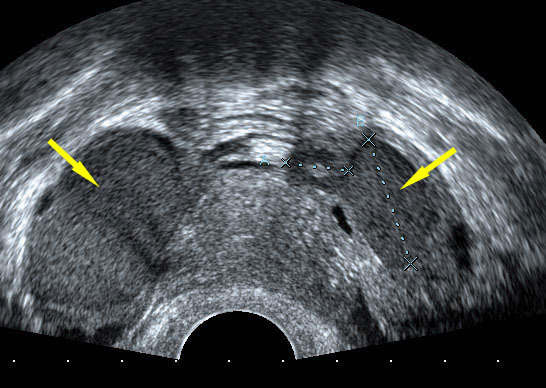

© Émile Daraï, Marc Bazot, Marcos Ballester (La Revue du Praticien)

Échographie endovaginale en coupe axiale passant par le col utérin montrant des kystes endométriosiques bilatéraux typiques. Tiré de : Darai É, Bazot M, Ballester M. Endométriose. Rev Prat 2010;60:603-9.